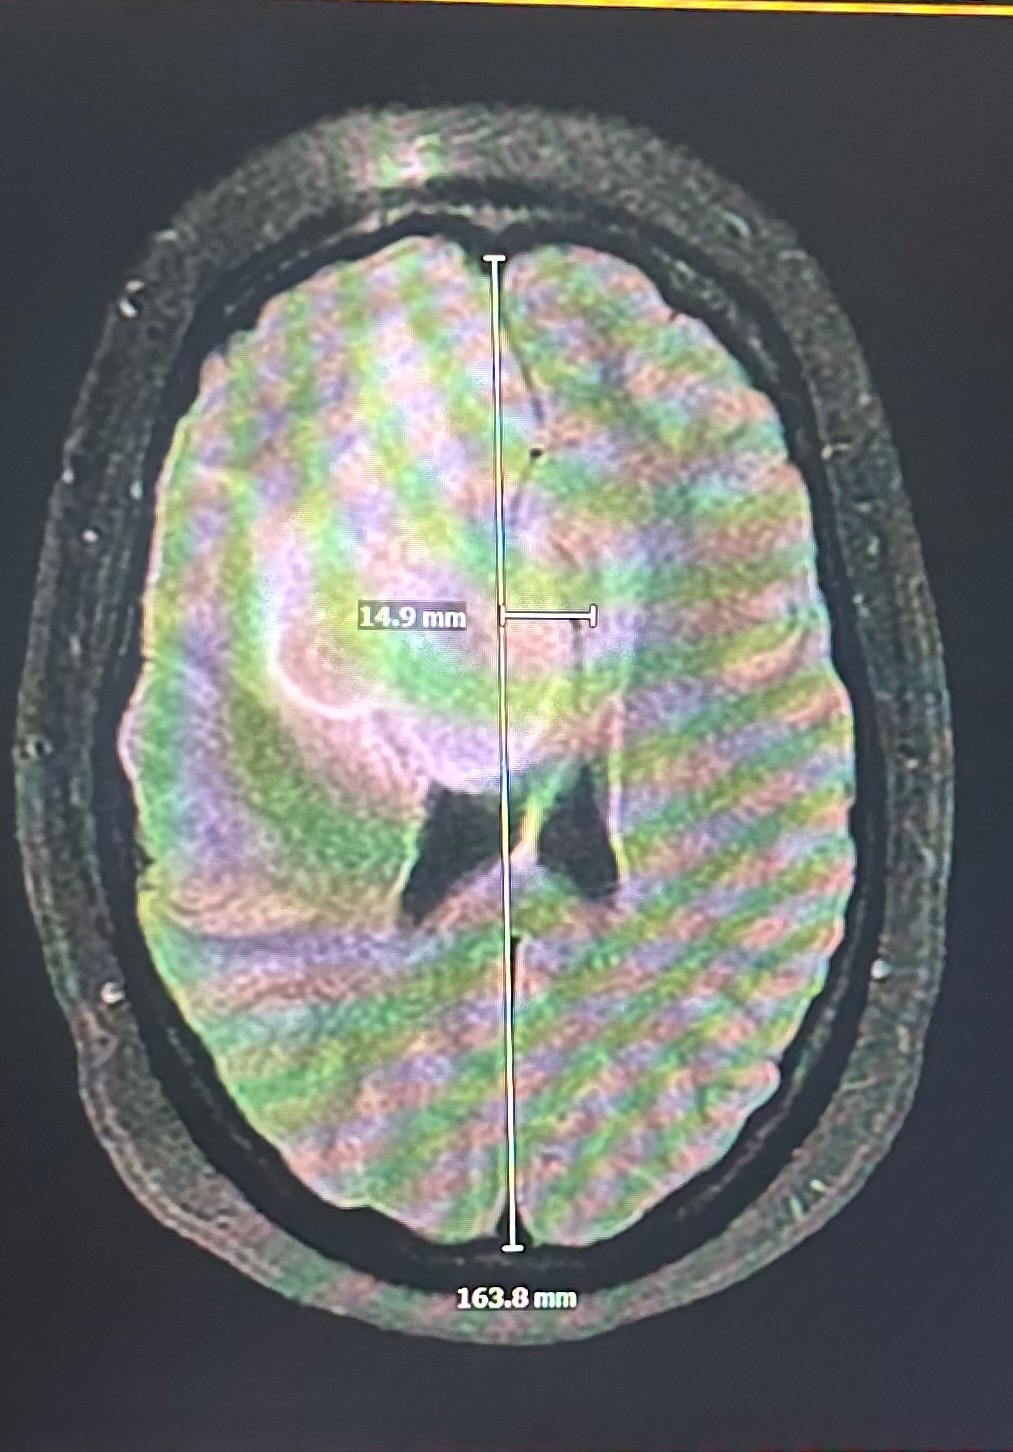

By 2am, she was admitted. After two nights, multiple doctors, and a series of tests, Sofia was told she would be having brain surgery Monday morning. The procedure was to remove a large mass located on her front right cortex — the cause of her migraines, which had already shifted her brain 15mm toward her skull. She was able to go home for the weekend to get some love from her dog Cotton and sleep in her own bed. In a beautiful act of taking control of her own story, she also chose to cut her hair — and Connor, Brinna, Madison, and Kurran joined her.